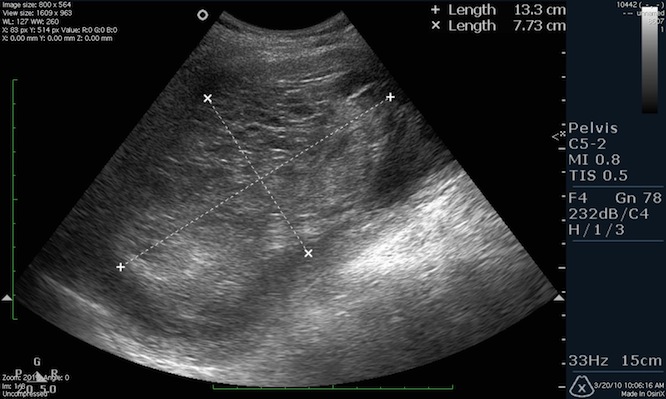

Ультразвуковое исследование покажет размеры матки, а опытный врач объяснит, каковы нормы ее размеров во время беременности, после родов и у девственниц. Фото УЗИ иллюстрирует размеры шейки матки, яичников и то, как выглядит матка, а врач даст полное описание изображению.

Осмотру подвергается тело матки, яичники, фаллопиевы трубы. Гинеколог при осмотре оценивает состояние матки, яичников и яйцеводов. Диагностике подлежит структура, форма, размер, толщина стенок, эхогенность, наличие визуально выраженных отклонений от нормы. Помимо этого, смотрят состояние шейки матки, ее длину и плотность.

При обследовании изучается расположение матки, ее форма, размеры и толщина стенок. Определяется состояние яичников и корректность их работы, проверяется наличие новообразований и жидкости в брюшной полости.

Размеры матки в норме у женщин, расположение органа, толщину эндометрия и расположение яичников позволяет наиболее точно выявить трансвагинальная диагностика. Для этого датчик, который представляет собой пластиковый стержень 12 см в длину, вводится на небольшую глубину.

Размеры матки в норме у женщин отличаются в зависимости от возраста, количества беременностей, абортов и гормонального фона. Специалисты измеряют длину и ширину матки, указывают толщину стенок.